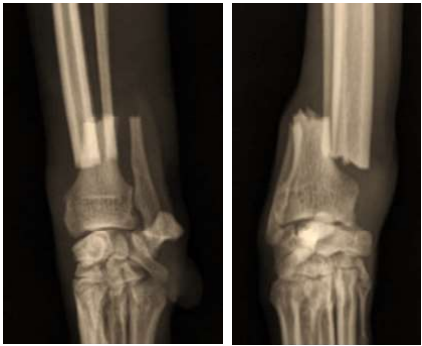

As radiografias abaixo pertencem a um Galgo Italiano, macho, com 5 anos de idade e 8 kg de peso corporal, que sofreu uma fratura fechada e não cominutiva do rádio ao saltar do colo do tutor:

Enunciado 4939637-1

A fratura será estabilizada com uma placa óssea de tamanho adequado. Considerando o tipo de fratura e as características do paciente, qual seria a função mais apropriada para a aplicação dessa placa?